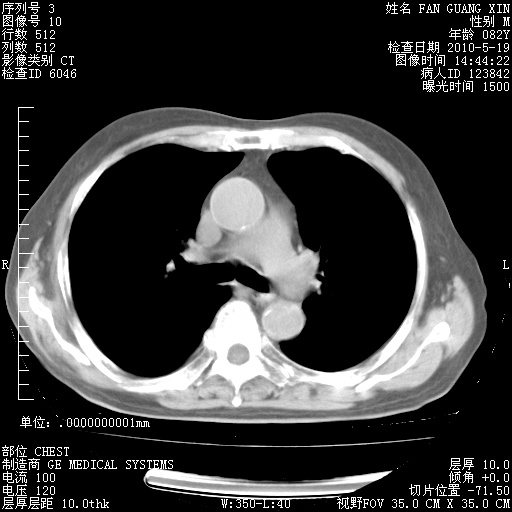

复查肺部CT,明显好转。为什么发热呢?

治疗3周后的肺部CT

治疗3周后的肺部CT纵隔窗